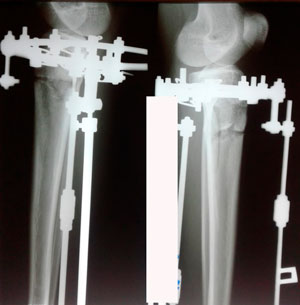

Исходник - 32 года.

Дата операции 28.01.2020

Вложения

IMG_8501-28-01-20-12-28.JPG

IMG_8506-28-01-20-12-28.JPG